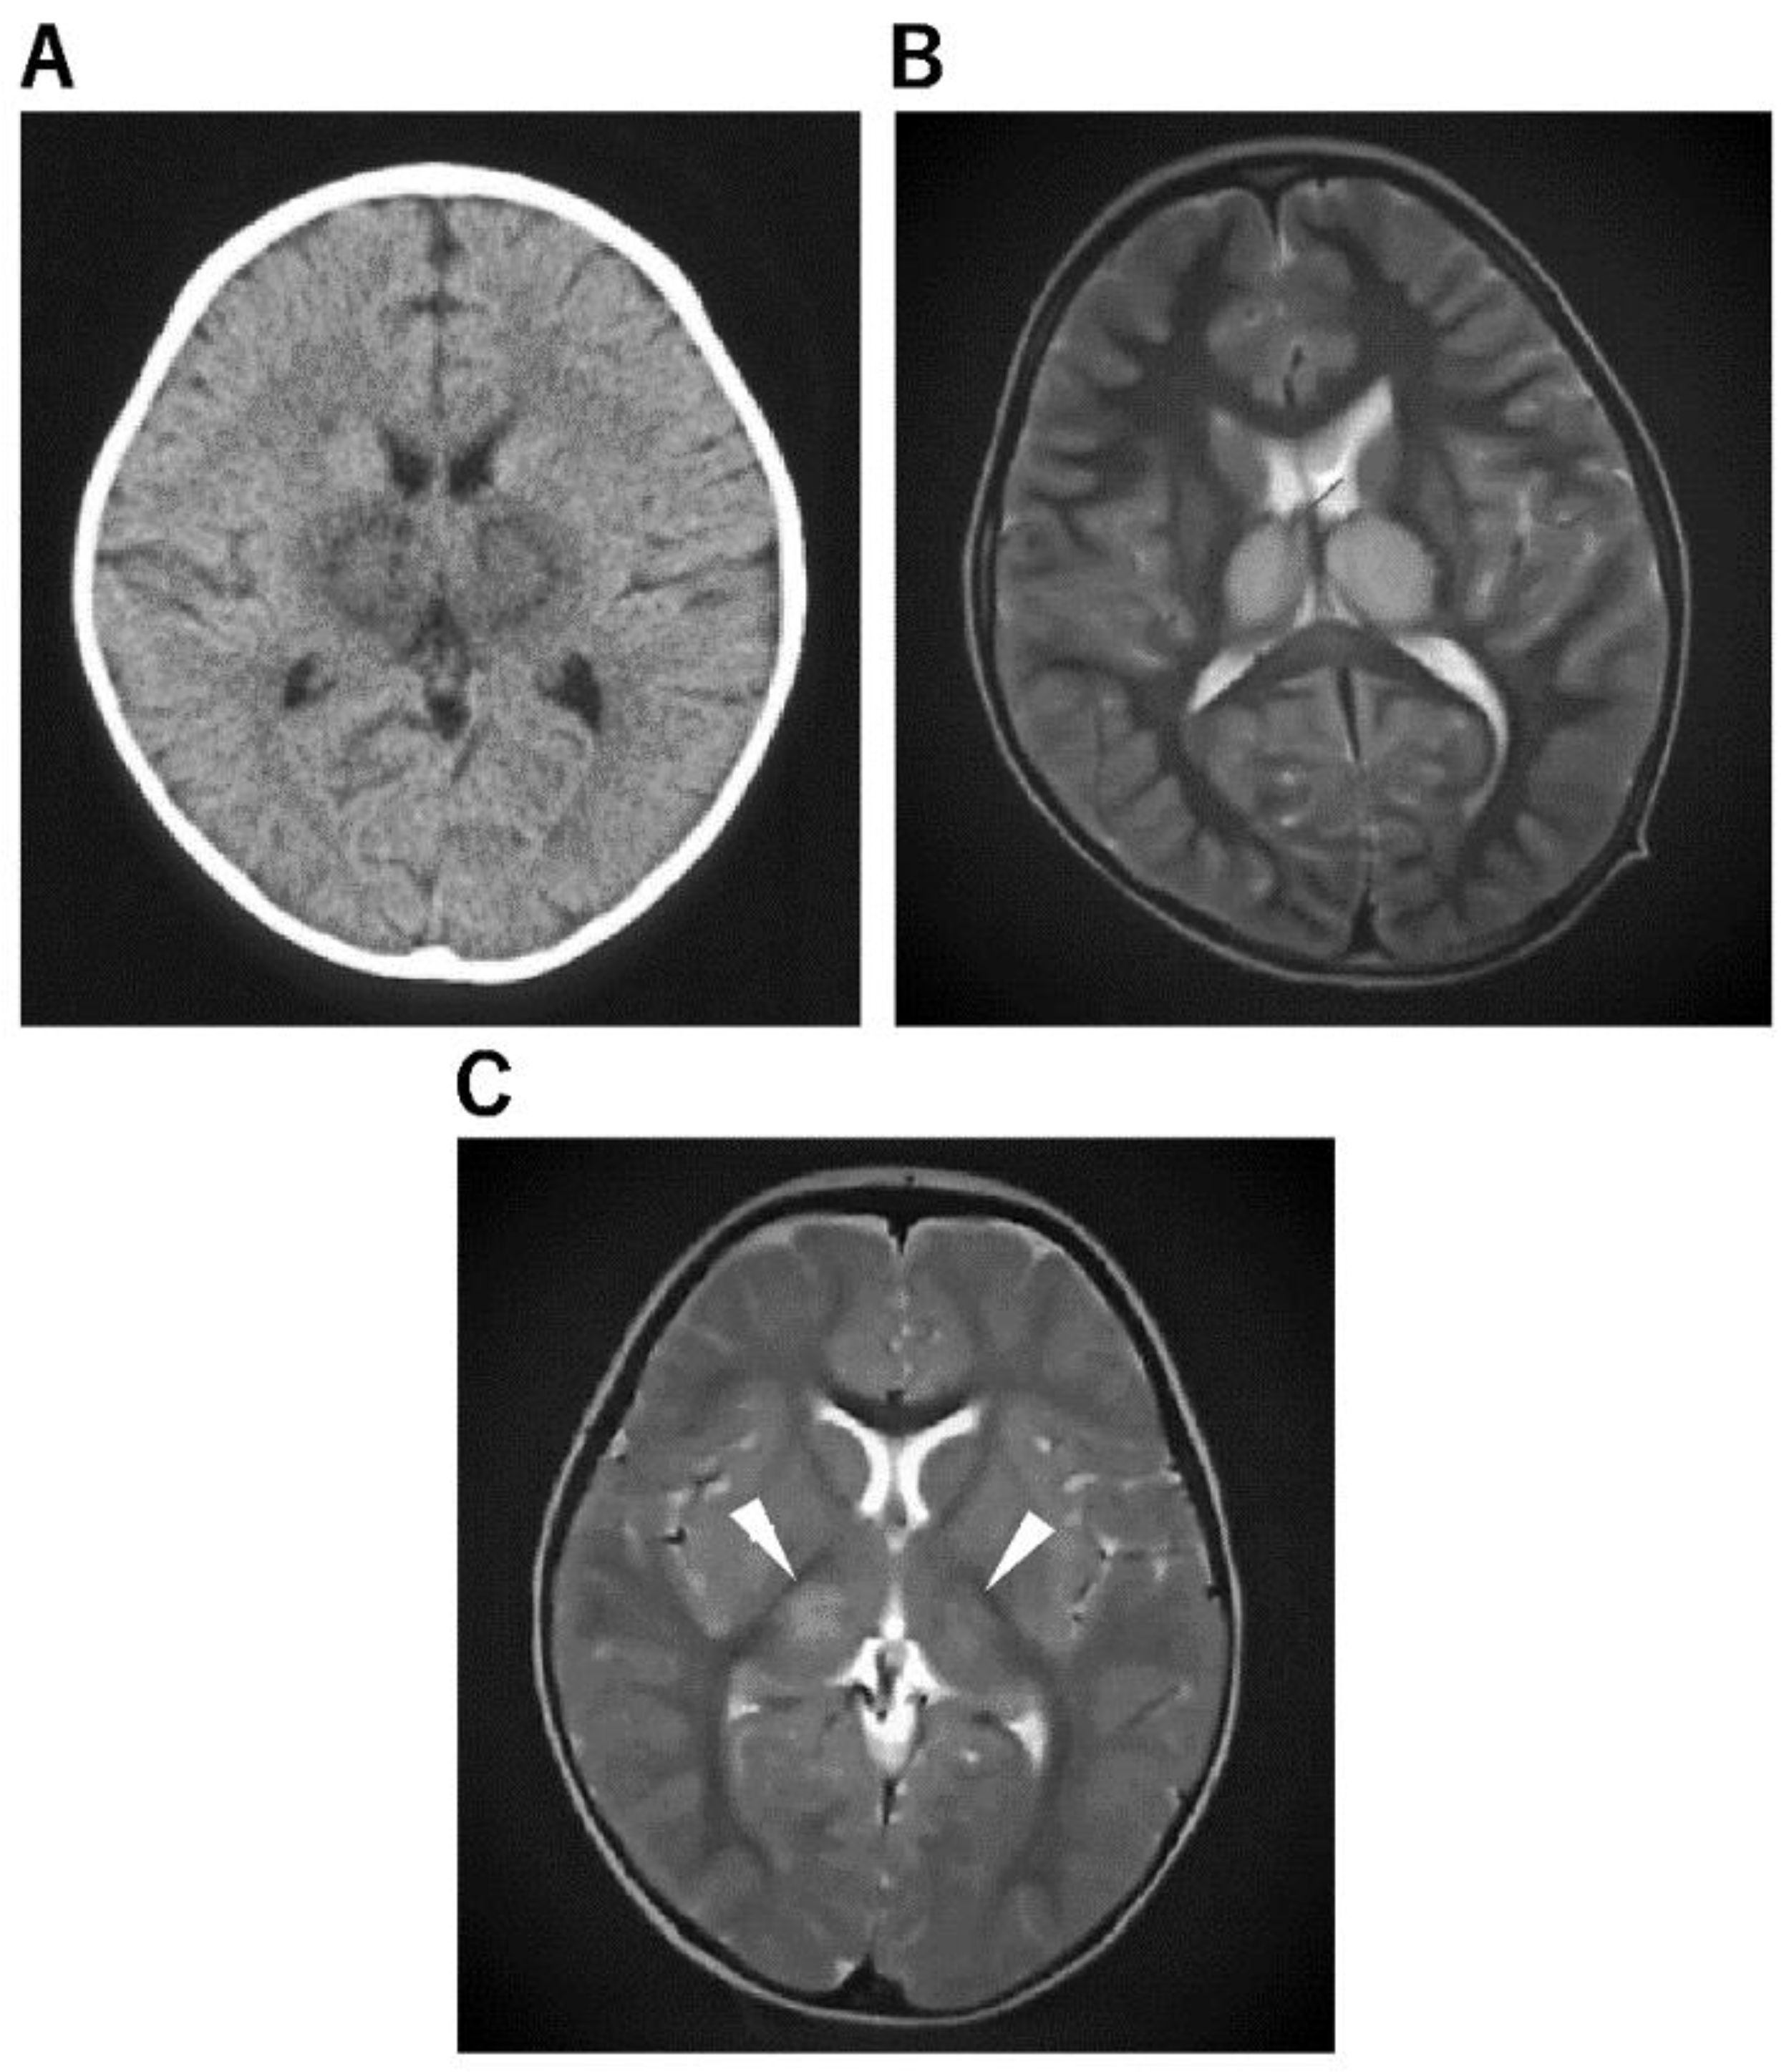

| Acute necrotizing encephalopathy (ANE) [52,53] | a. Concentric structure of the thalamocerebral lesions; diffuse cerebral edema and symmetric and multifocal lesions in the thalamus and other CNS regions, including the posterior limb of the internal capsule, posterior putamen, cerebral and cerebellar deep white matter, and upper brainstem tegmentum. b. The thalamic lesions often show hemorrhagic degeneration and cystic change after 3 days, showing a high signal on T1WI and a low signal on T2WI or T2 star-weighted imaging. |

| ANE [82,83,84] | ||||

| Multiple bilateral brain lesions, primarily involving the thalami, but also involving the putamina, internal and external capsules, cerebellar white matter, and the brainstem tegmentum. | Many cases have been reported in Asia as well as in a number of Western countries. | Dramatic neurological deficits/symptoms. Neurological deficits may be preceded by a viral prodrome. | Associated thalamic, putamina, cerebral, cerebellar, and brainstem abnormalities are hypodense on CT. Bilateral symmetrical thalamic involvement. Abnormal signals on MRI are hypointense on T1 and hyperintense on T2. Restricted diffusion of the involved regions. ANE of childhood can be distinguished from ADEM clinically by the onset of encephalitic features shortly after the prodromal illness, whereas in ADEM, they may take 1 to 2 weeks to develop. | Immunomodulatory therapy such as corticosteroids or intravenous immunoglobulin is often used. TTM has also been used. TTM is critical to the outcome of children with ANE, especially if started within 12 h of onset. |